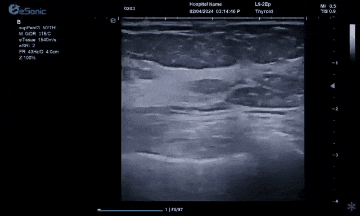

利来国国际网站医疗(ESI)表示,其最新的人工智能功能可以帮助到医疗机构的工作效率,功能包括,实时、动态、快速自动识别病灶,良恶性病灶概率预测,甲状腺结节和乳腺的二维灰阶动态自动实时检测需求,提供多个结节动态检测轮廓框。实时获取多幅具备临床特征(大小、属性等)的结节切面,同时提供当前切面所示结节的结节大小、属性特征、TI-RADS 分级。

对于甲状腺结节相关的自动检测功能,甲状腺结节病灶检出率≥95%,良恶性分类灵敏度≥90%、良恶性分类特异度≥85%。